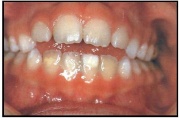

Emaili hüpoplaasiad

muutused hammaste kujus